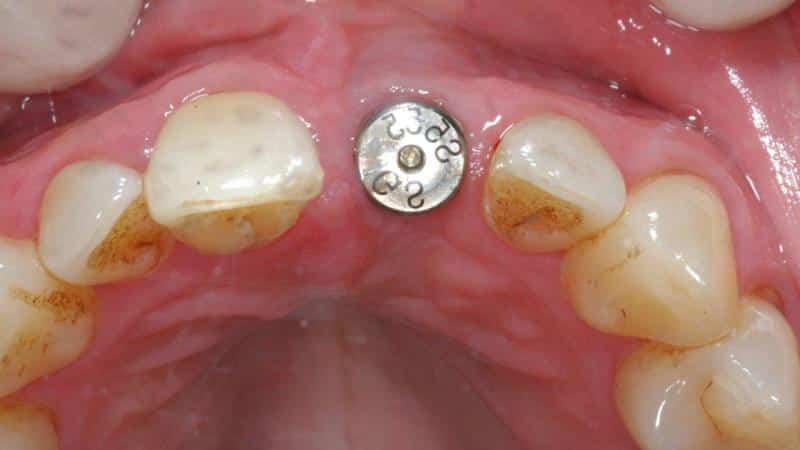

Что такое формирователь десны при установке имплантатов? Этот вопрос интересует многих, кто решил сделать имплантацию. Формирование десневых тканей — это важный этап в процессе имплантации. Данный компонент представляет собой толстый металлический цилиндр с винтовой конструкцией и резьбой, изготовленный из гипоаллергенного титана или циркония. Он оснащен специальной цилиндрической головкой, которая может различаться по длине и диаметру. Стоматолог устанавливает его после успешного внедрения имплантата. Формирователь десны помещается в десну для создания углубления вокруг будущей коронки имплантата. Это обеспечивает плотное прилегание искусственной коронки к десне, что способствует эстетике как протеза, так и десны.

Операция выполняется под местной анестезией и занимает не более одного часа. Существует два основных метода: одномоментный и стандартный. В первом случае формирователь устанавливается сразу после имплантации, а во втором — через несколько месяцев, с необходимостью надреза и удаления мягких тканей. В некоторых случаях может потребоваться наложение швов для ускорения заживления. Чтобы лучше понять процесс установки формирователя десны, можно ознакомиться с фото, иллюстрирующими эту процедуру. Вся операция проходит в три этапа: установка имплантата, формирование десны и протезирование. При простых вмешательствах этапы могут быть объединены, однако для достижения наилучшего результата, который обеспечит долговечность и эстетичность, приближенную к натуральным зубам, лечение рекомендуется проводить поэтапно.